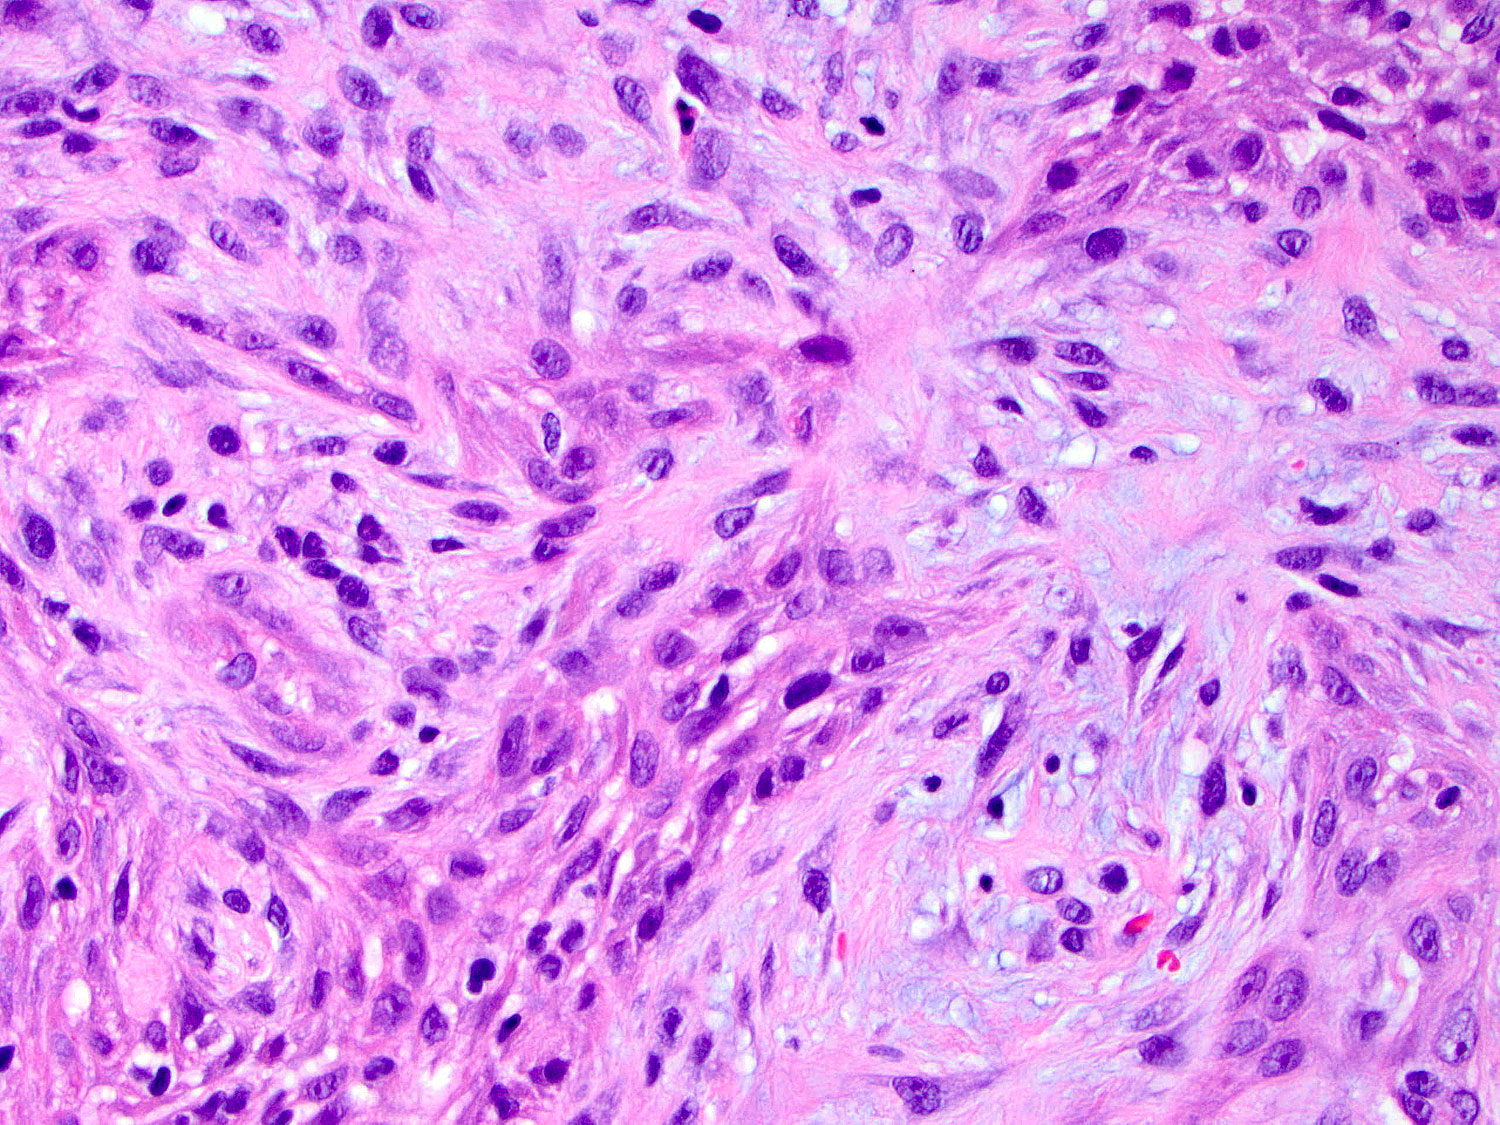

H&E staining (40x objective)